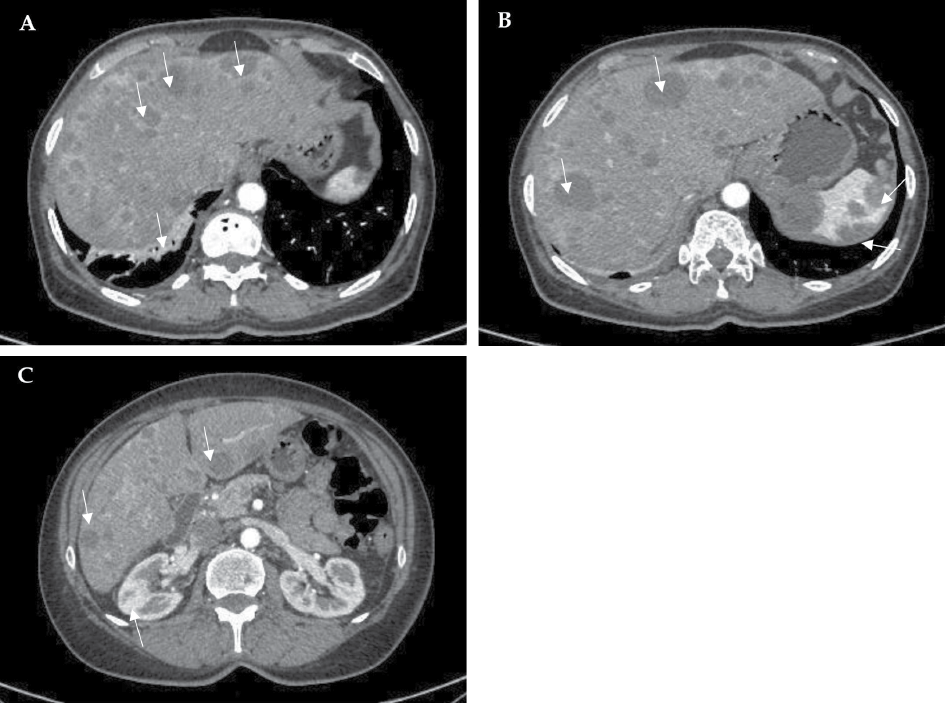

Metastatic foci were confirmed by performing a full-body computed tomography (CT) scan, which showed hepatomegaly (right lobe ~184 mm), multiple hypodense solid diffusely distributed masses in the liver (to 3 cm in diameter), spleen (to 3.7 cm in diameter), and kidneys (to 12 mm in diameter), moderate interstitial, para-aortic, paratracheal, and aortocaval lymphadenopathy, and disc atelectasis in the lungs (Figure 2, A–C).

Figure 2. Computed tomography images. Multiple hypodense solid diffusely distributed masses (arrows) in the liver (A–C), spleen (B) and kidneys (C); disc atelectasis in the right lung (arrow) (A).